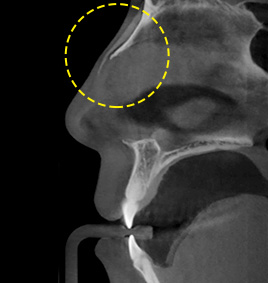

3D-CT nose surgery involves identifying not only the external parts of the nose but also symptoms and causes of nasal bone, crooked nose, nasal septal cartilage, nasal congestion, etc. As three-dimensional analysis using 3D-CT helps establish an adequate surgery plan and reduce damage to blood vessels and nerves, safe and precise operation can be performed.

3D-CT analyzes the nose three-dimensionally.

FACE uses advanced 3D-CT equipment to analyze the overall condition of nasal bone, nasal septal cartilage, skin tissue, asymmetry, etc.,

which cannot be identified by general consultation,

in order to secure safer and more precise nose surgery.